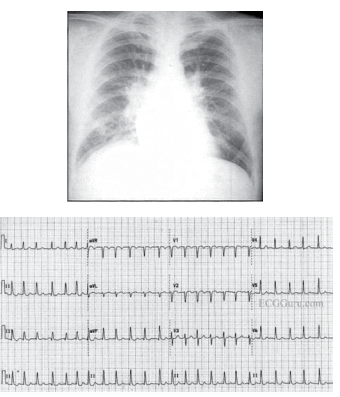

O mecanismo fisiopatológico que melhor explica a descompensação clínica dessa paciente é

A melhor abordagem terapêutica inicial consiste em administrar

Em relação à investigação diagnóstica complementar, é correto afirmar que

A terapêutica inicial apropriada ao caso em questão deverá incluir